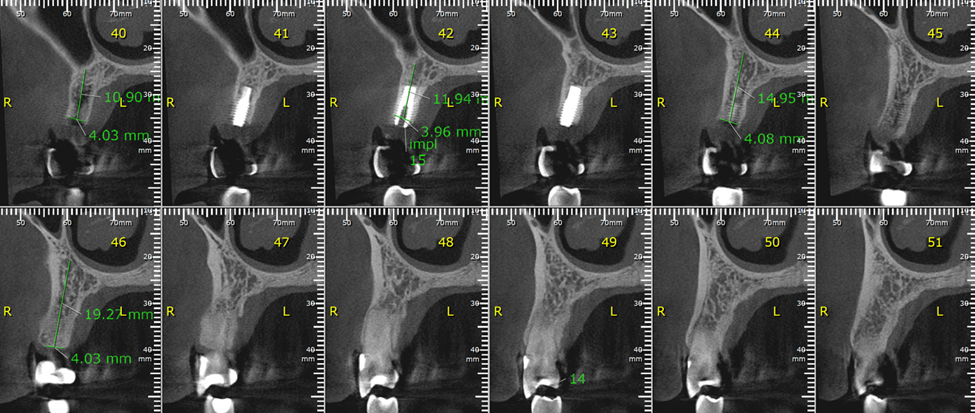

No presente caso, o paciente procurou nossa clínica acreditando que a coroa sobre implante do 15 estava apenas frouxa, e que seria possível resolver apertando o parafuso. Ao exame clínico, apresentava uma coroa cimentada sobre componente UCLA fundida e parafusada diretamente sobre o hexágono do implante (um HE de 3.5 mm de diâmetro e plataforma da mesma medida). Após o corte da coroa para acessar o parafuso, na remoção do conjunto, a plataforma do implante veio anexada à coroa, denotando a fratura do implante, que foi comprovada com radiografia periapical (Figuras 1 e 2). Decidimos por fazer uma prótese adesiva provisória (Figuras 3 e 4) e planejar a remoção do implante com colocação imediata de novo implante, após observado na tomografia cone beam que haveria osso suficiente para isso (Figura 5). O implante foi removido (Figuras 6 e 7) com o uso de broca trefina e fórceps, e um implante Implacil De Bortoli CM Due Cone foi instalado no mesmo momento (Figura 8), com regeneração óssea guiada (ROG) na parede vestibular (Figura 9), que havia ficado muito fina (enxerto ósseo particulado + membrana de colágeno). Apesar de termos obtido bom travamento do implante (45 Ncm), optamos por deixá-lo sem carga pelo período de cinco meses, para respeitar o tempo da ROG (Figuras 10 e 11).